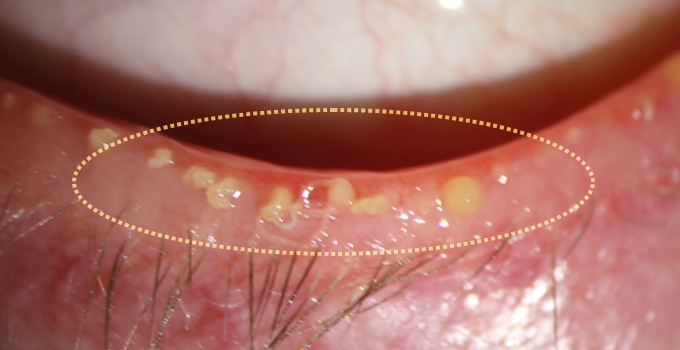

• 시술 시술

시술 전